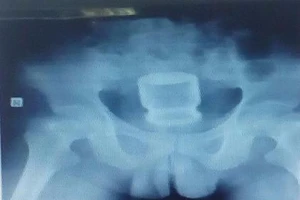

Nghe lời lang băm, nhét cốc vào mông chữa... dạ dày